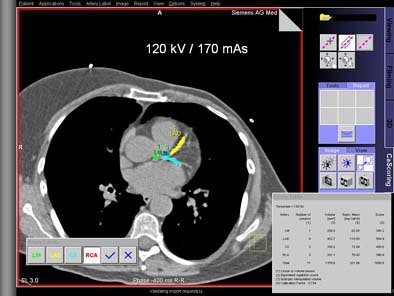

Moving to the human portion of the study, Schoepf, along with colleagues Dr. Jens Martensen, Dr. Kelly Zou, Dr. Bernhard Schmidt, Dr. Stefaan Ulzheimer, and Willi Kalender, Ph.D., scanned 20 asymptomatic subjects using the same 16-slice Siemens scanner as used in the phantom study, at 120 kVp and at 170 mAs, and using a retrospective ECG gating protocol.

"Since you can’t scan those patients multiple times, we used a software platform to add artificial image noise," Schoepf said. The Vamp syngo Explorer application was applied to the resulting images to simulate reduced mAs of 150, 130, 110, 90, 70, and 50 in consistent regions of interest over the left ventricle. All three methods of calcium scoring were again applied in the usual manner at all noise degradation levels. Scoring variations at low-dose settings were again compared to those at the full dose, he said.

| Top, patient was scanned with 120 kVp/170 mAs. Below, artificial image noise was added using the Siemens Vamp syngo Explorer to simulate acquisition with lower dose settings at 120 kV/110mAs and 120kV/50 mAs. Calcifications in the left main coronary artery are highlighted in green, those in the left anterior descending coronary artery in yellow, and those in the left circumflex coronary artery in blue. The calcium scores at the three dose settings are not significantly different. Images courtesy of Dr. Joseph Schoepf. |